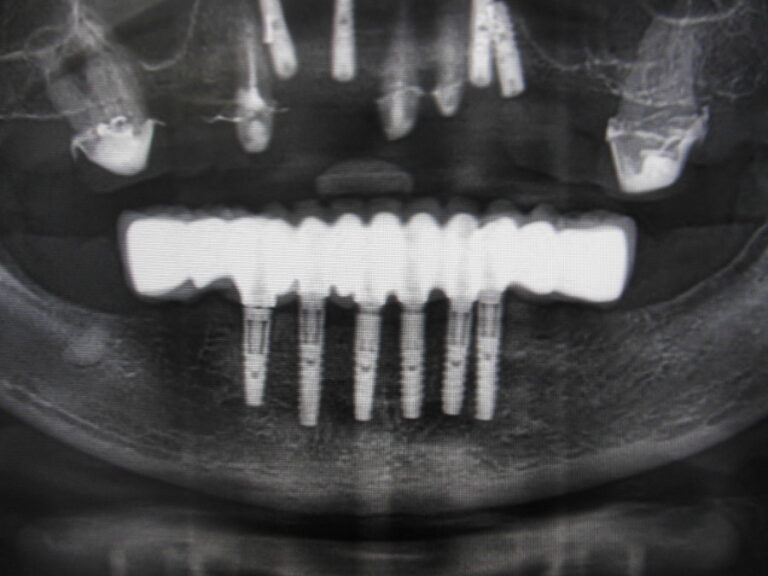

Implanty zygomatyczne

Przykłady implantologii

Zastosowanie implantoprotetyki w przypadku gdy klasyczna protetyka nie sprawdza się.